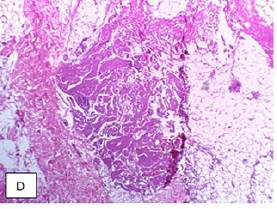

Debido a la presencia de alteración renal se sospechó compromiso renal de la sarcoi-dosis vs amiloidosis secundaria. Se tomó entonces biopsia de grasa parda abdominal y se realizó tinciones con rojo Congo y hematoxilina - eosina, que evidenciaron material amiloideo (foto 4), configurando así el diagnóstico definitivo de sarcoidosis y amiloidosis reactivas, por lo que se decidió iniciar manejo con cloroquina, presentando adecuada evolución, mejoría de sus síntomas y de la hipercalcemia.

Su asociación con sarcoidosis ha sido reportada y se destaca la proteinuria entre los hallazgos más usuales 17. En el paciente descrito llamaba la atención la proteinuria con sedimento blando, lo que hizo sospechar el compromiso. La biopsia de grasa subcutánea abdominal se escogió por un mejor rendimiento y por la necesidad de una buena sensibilidad para evitar procedimientos adicionales 3. Consideramos que el compromiso renal era secundario a la amiloidosis, aunque no fue posible confirmarlo ya que no se realizó biopsia renal.